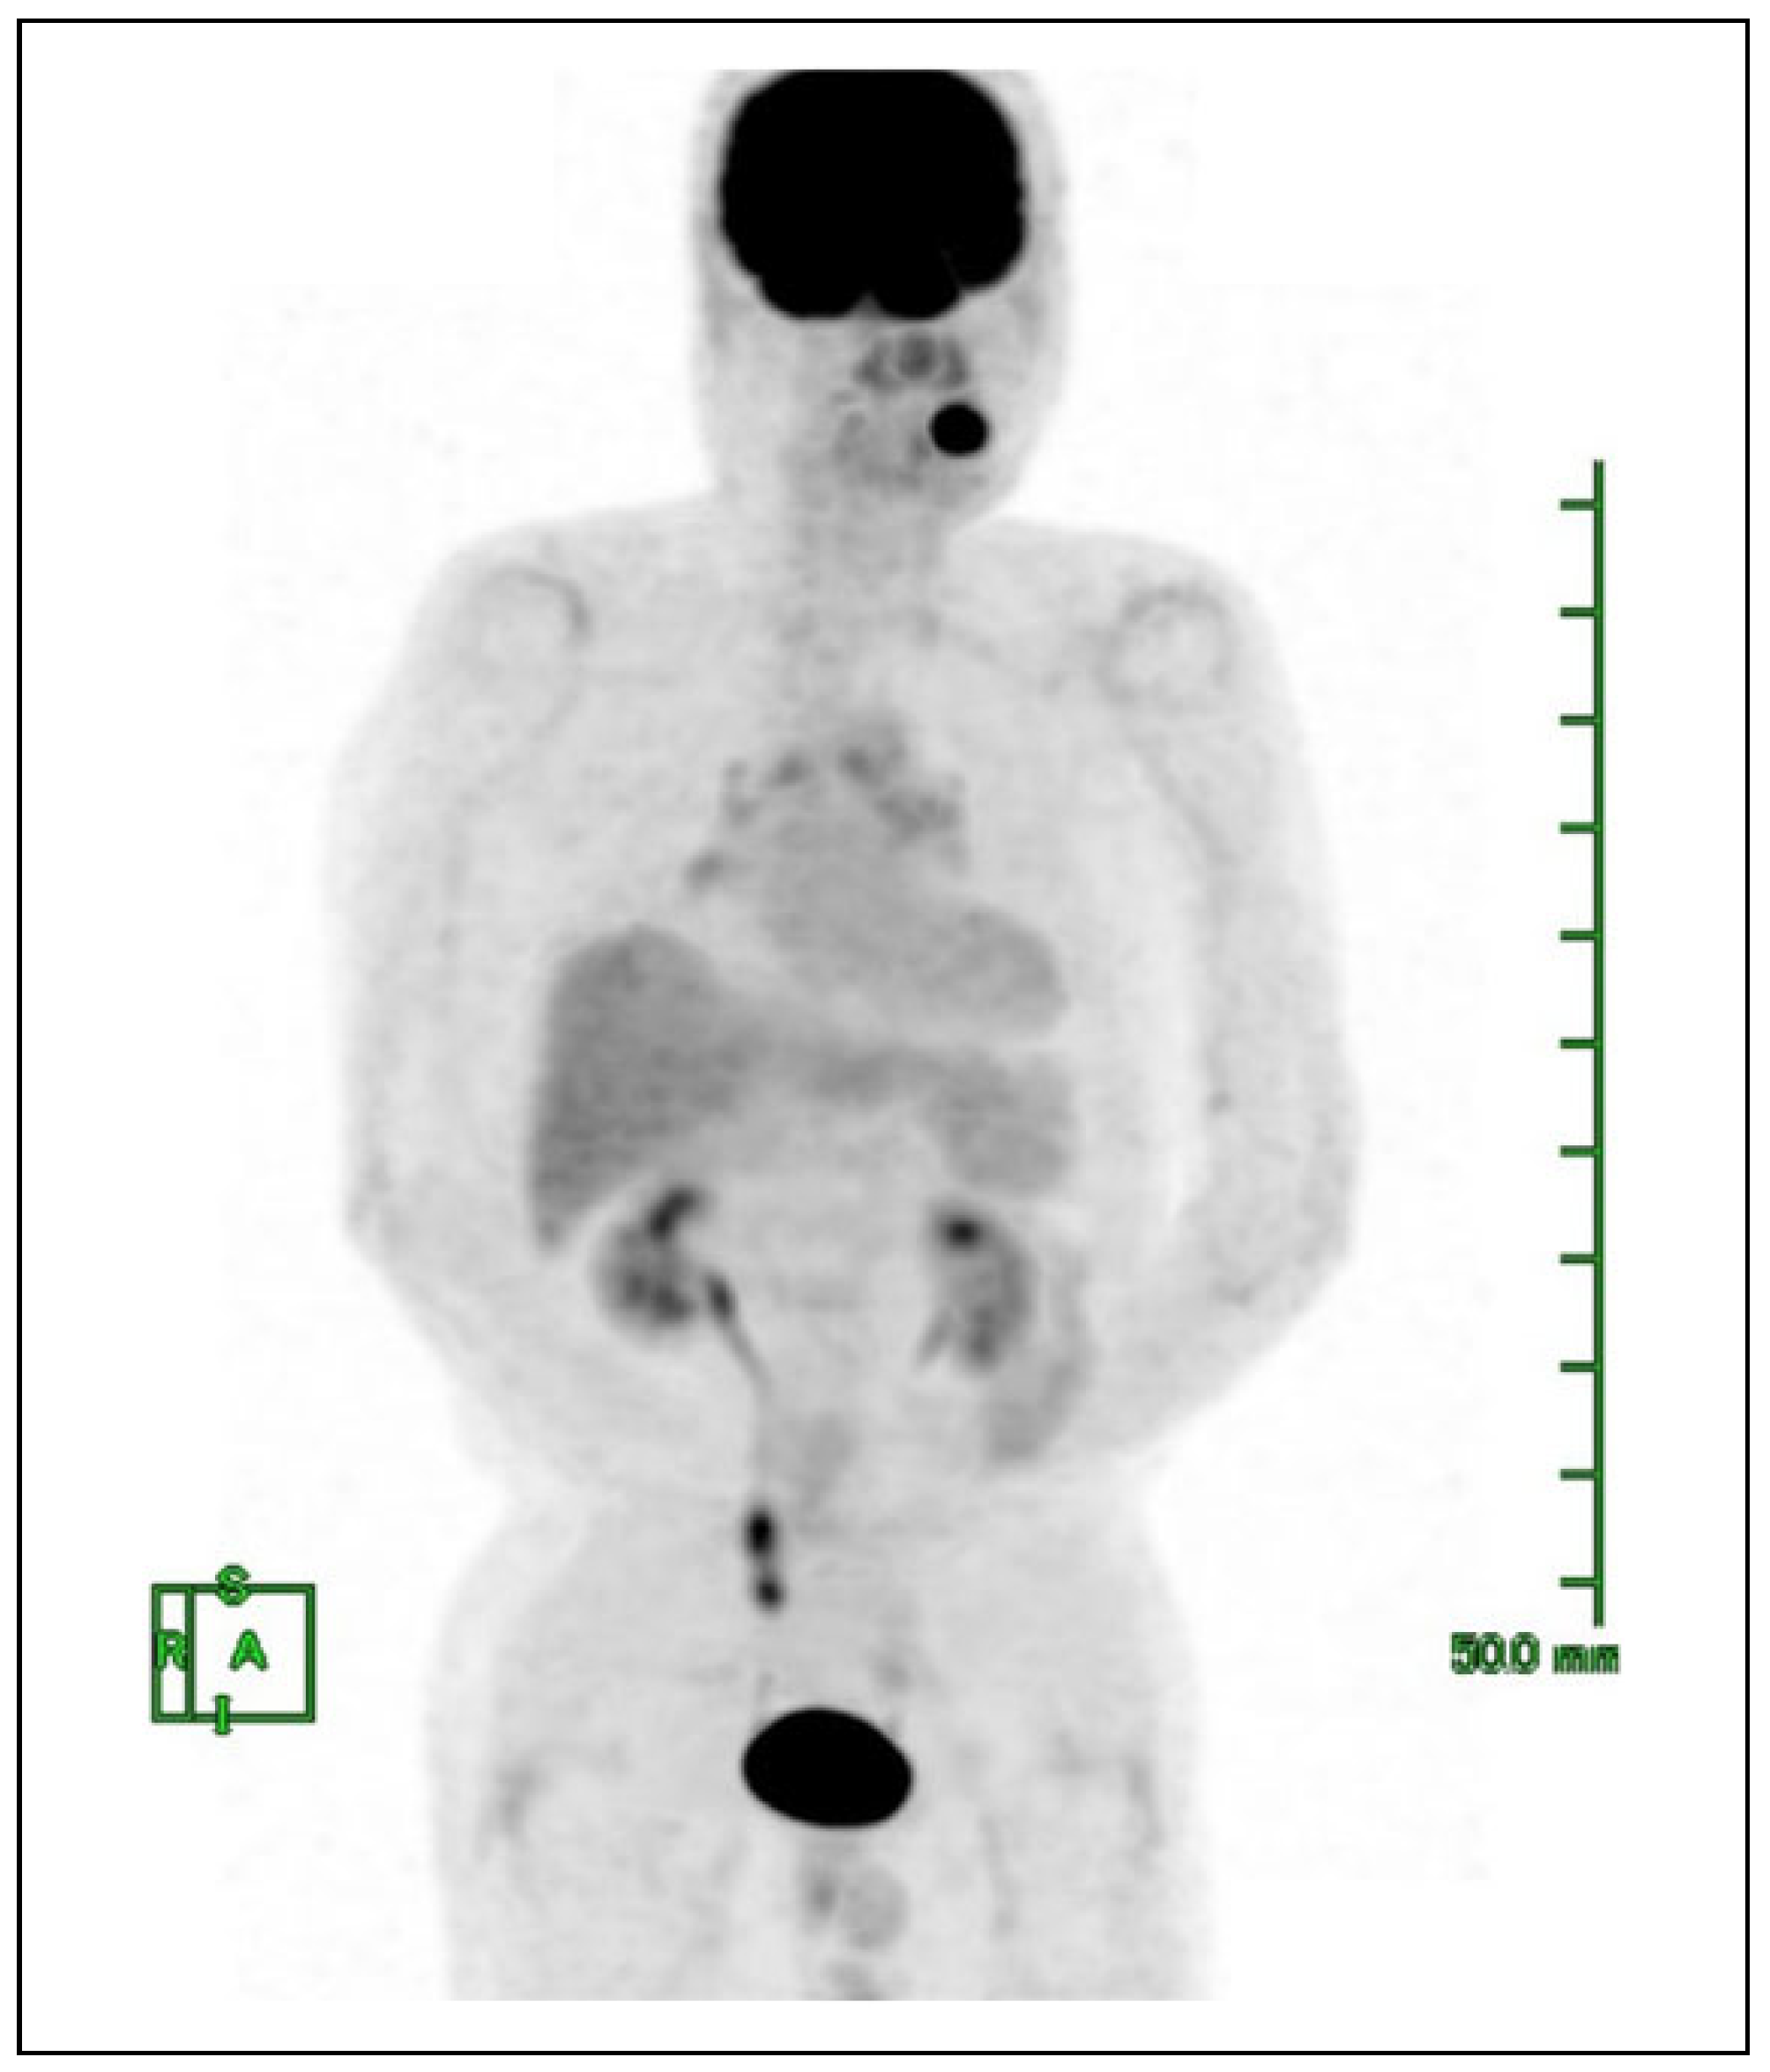

Case Presentation

Postoperative Course